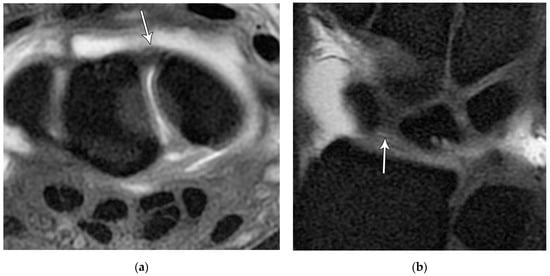

Figure 22. (a) Axial T1 FS MR arthrogram images showing a normal thick dorsal scapholunate ligament (arrow). (b) In a different patient, coronal T1 FS MR arthrogram images showing a normal thick dorsal scapholunate ligament (arrow).